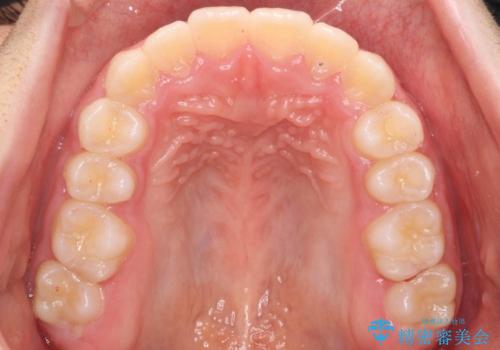

八重歯 歯を抜かずにインビザラインで

- 八重歯を主訴に来院。

抜かずに歯を少し削って入れる方法で並べました。

10代のうちに矯正をしておくと歯の移動は簡単で、歯ぐきも下がりにくいです。

乳歯が永久歯に生え変わるまで成長観察を続け、永久歯列になってから治療開始しています。